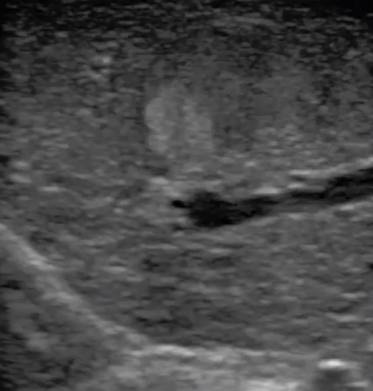

3  腹腔鏡超聲探頭

腹腔鏡超聲是超聲技術(shù)和腹腔鏡技術(shù)的融合,腹腔鏡超聲降低了對超聲探測深度的要求。由微小切口進入手術(shù)部位,多角度彎曲可選擇,降低手術(shù)難度及風險;與受檢組織器官直接接觸,有效避免氣體干擾。

應(yīng)用科室:麻醉科、手術(shù)室、普外科、泌尿外科、婦產(chǎn)科、腫瘤科、介入科等

腹腔鏡下 肝臟占位